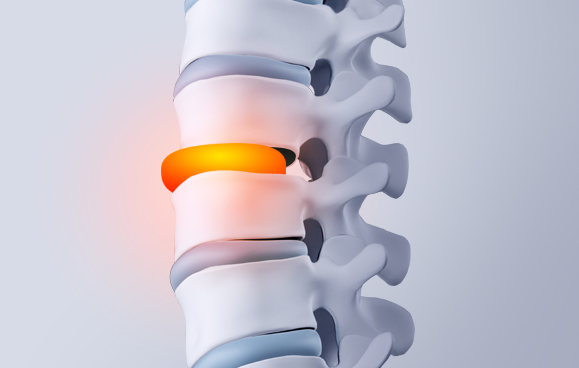

허리디스크(요추 추간판 탈출증)는 허리 디스크가 돌출되면서 신경을 자극해

허리에서 엉덩이, 다리로 통증·저림이 내려갈 수 있습니다.

오래 앉아 있거나 허리를 숙일 때, 기침·재채기처럼 힘이 들어갈 때

다리 증상이 심해지는 경우가 있어 평가가 필요합니다.